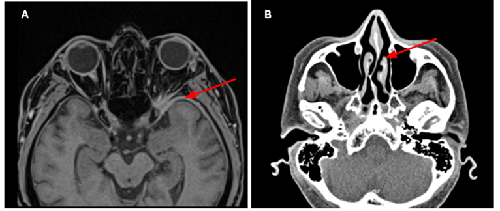

- Evaluation of Plasma-Assisted Noninvasive Surgery (PANIS) As a New Approach for Pterygium Removal with Amniotic Membrane Transplantation (AMT); a Clinical Case Series610.23958/ijirms/vol06-i11/1258